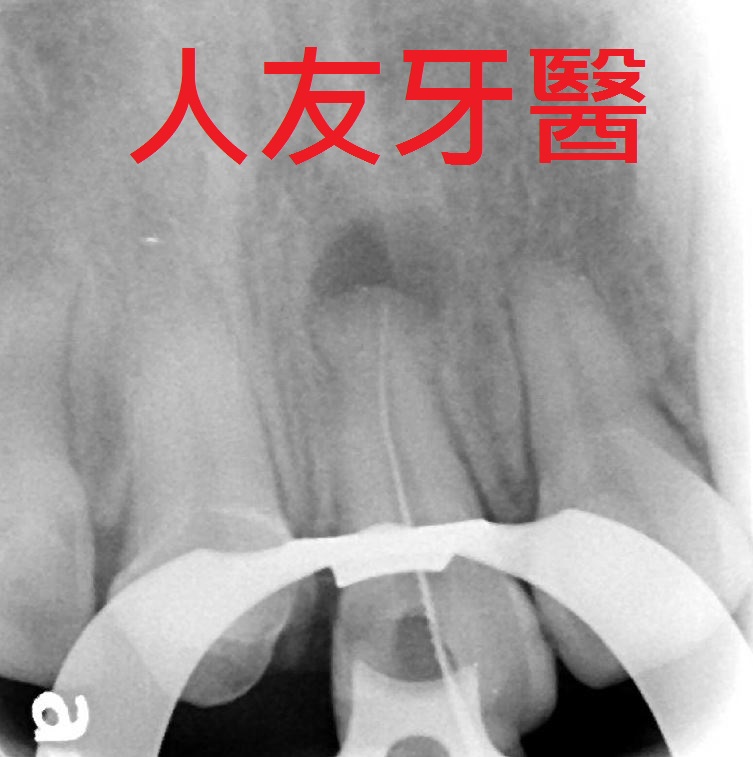

而左側門牙根尖有一個病變,醫師透過根管治療的方式把牙根深層的細菌清除乾淨,放入柱心補強,最後再搭配牙套保護.

想詢問周醫師如何處理。醫師看了X-RAY發現右邊側門牙紅色圓圈的地方有病變,有可能留不住。左邊側門牙藍色箭頭牙齒有裂到肉,也可能留不住。經過討論後建議都拔除。